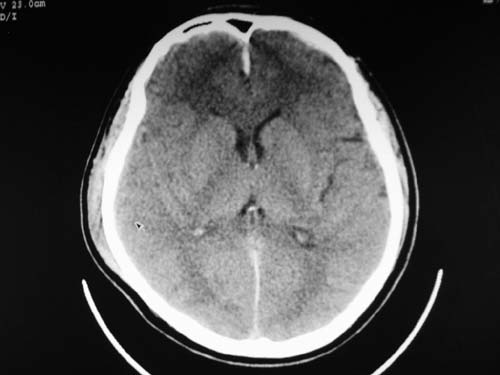

标题: CT17020:是硬膜下的吗?

脑中线内血肿,是硬膜下的吗?

脑中线内血肿——硬膜下血肿。

脑中线内血肿——硬膜下血肿。我们一般认为中线即可是硬膜下,也可是蛛网膜下腔的。边缘锐利,张力高的考虑硬膜下的,边缘模糊的,考虑下腔的。如果有老师有肯定的答案,麻烦下给我发个短信

这个病人年龄不小吧,右侧脑沟不清,中线结构稍有左移,右侧额颞顶及右镰旁硬膜下血肿,另有蛛血,骨折。

外伤后引起的颅骨骨折、硬膜下血肿、皮下血肿,颅骨骨折引起的矢状窦破裂,形成大脑纵裂内血肿。